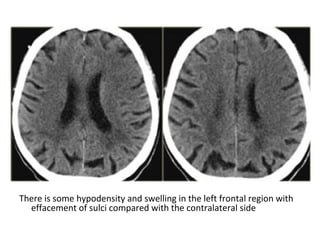

Normal GWM differentiation Loss of GWM differentiation

There is some hypodensity and swelling in the left frontal region with

effacement of sulci compared with the contralateral side